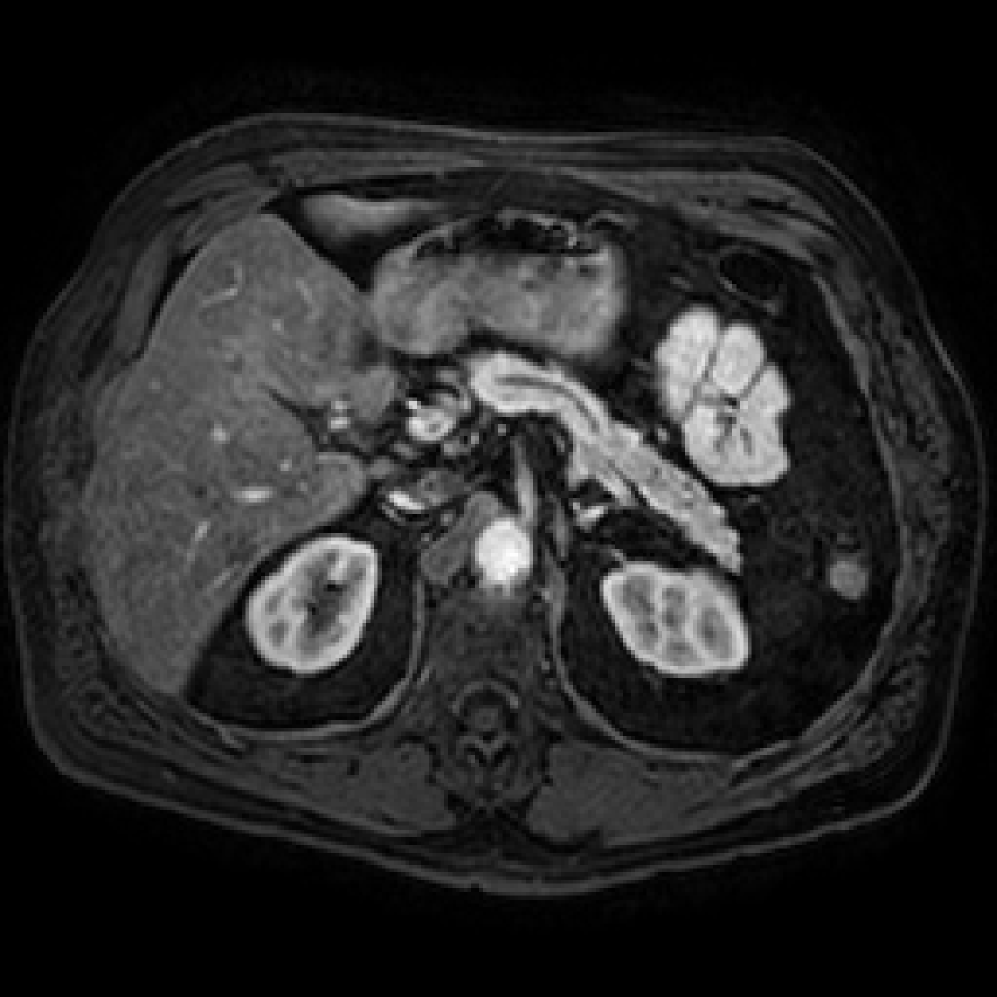

Accurate pancreas segmentation is a critical prerequisite for precise cyst analysis and classification. Recently, we developed PanSegNet [zhang2025large], a novel segmentation architecture incorporating linear self-attention layers [zhang2022dynamic] within the nnUNet framework [isensee2021nnu] to enhance global information modeling capabilities while maintaining computational efficiency (Fig. 1). PanSegNet demonstrated exceptional segmentation performance across both T1W and T2W modalities, achieving mean dice scores of 86.817.30% and 89.626.38%, respectively (Table 1, Fig. 2b-c). This performance significantly exceeded that of Swin-UNETR [hatamizadeh2021swin], one of the most used state-of-the-art transformer-based medical segmentation models, which achieved dice scores of 79.091.40% and 76.290.66% for T1W and T2W, respectively (). In this study, we integrated PanSegNet into our Cyst-X engine along with a classifier for risk prediction. In Section 2.2, we show that the choice of segmentation model affects the classification results. The performance advantage of PanSegNet was consistent across all seven medical centers, demonstrating robust generalization despite variations in imaging protocols and equipment (Table 1). This cross-institutional reliability is particularly important for clinical applications, where model performance must remain consistent regardless of imaging site or acquisition parameters.

Each patient was categorized into one of these three ground truth classes: no risk/control, IPMN low-risk, or IPMN high-risk. To evaluate variability in image acquisition, we applied uniform manifold approximation and projection (UMAP) to image quality indicators, revealing distinct clustering patterns by imaging center and slice thickness. This heterogeneity reflects real-world clinical variability, enhancing the dataset’s generalizability while presenting technical challenges for model development. Fig. 6 shows examples of low-grade, high-grade, and cancer developing IPMNs from the Cyst-X dataset.